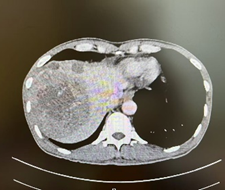

新辅助治疗前CT

该病例是张继红医生在佛山复星禅诚医院肝胆胰外科亲自收治和主刀的手术病例。男性50岁病人,因消瘦、纳差2月入院。病人既往有乙肝病史多年。入院后经B超、CT检查诊断为肝细胞癌,多发性,有两个瘤体巨大,长径分别为11.0cm和8.0cm,周围多子灶。